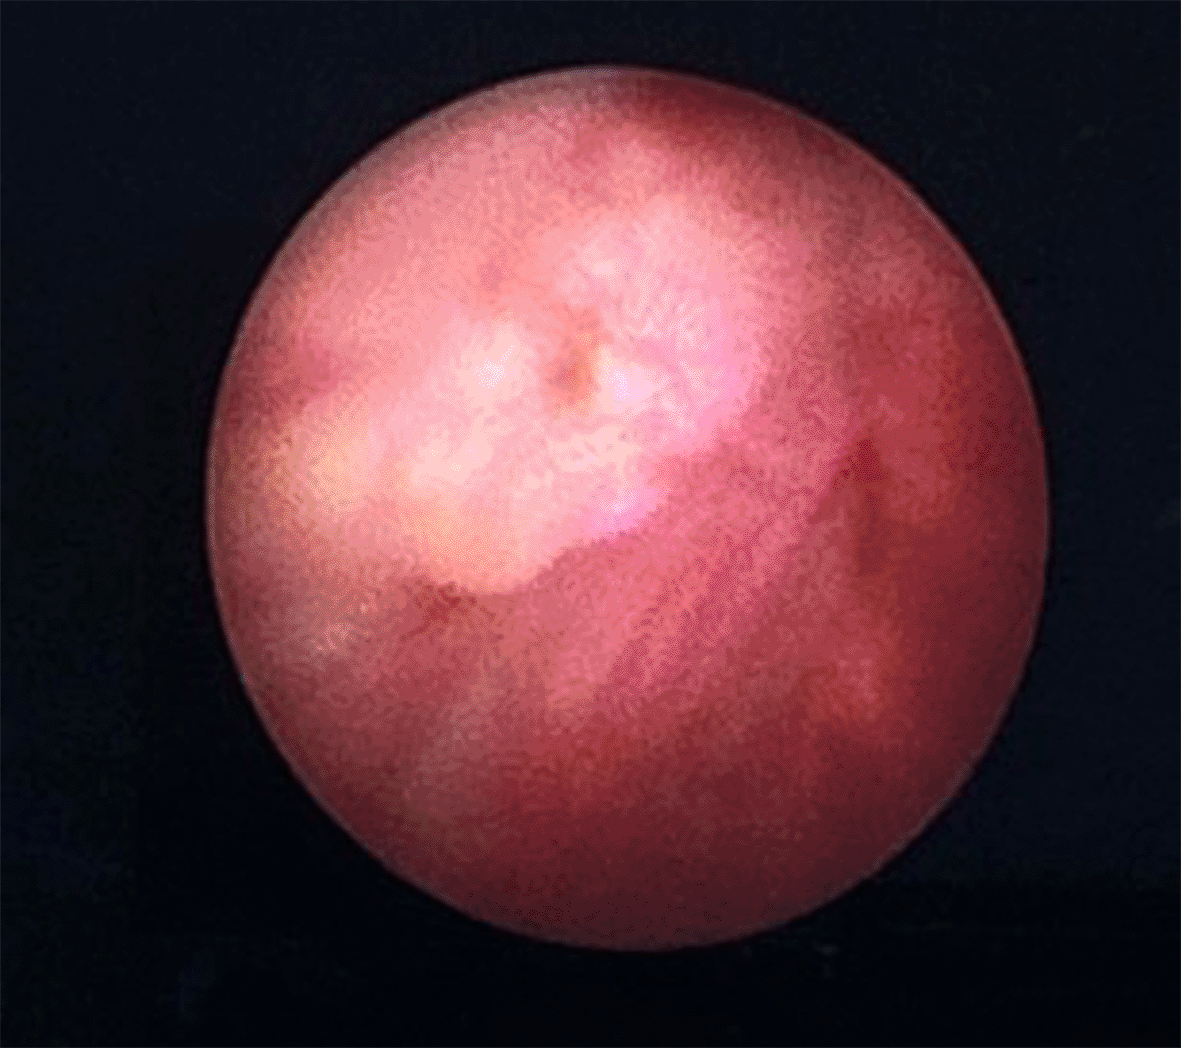

The patient was scheduled for a cystoscopy and urethral mass excision two days later. Cystoscope was inserted through the cystostomy access, showing a tumor infiltration to the anterior wall of the bladder approximately 2 cm from the bladder neck ( Figure 3). Due to highly suspicious lesions of malignancy based on visual, endoscopic, and imaging appearance, we didn’t perform preoperative biopsy and proceeded to definitive surgery. Radical urethrectomy and partial cystectomy were then performed through a transurethral approach with antegrade cystoscopy guidance. This method was used to make sure the tumor completely resected since we do not have frozen section facilities in our hospital. The excision was extended to the bladder neck and a portion of the anterior segment of the bladder wall which infiltrated by the tumor. We decided to do the bladder preservation and bladder neck reconstruction using remaining anterior bladder wall with the intention to facilitate voiding through the orthotopic site with a Foley catheter, thereby avoiding the need for a permanent suprapubic diversion. The tumor-free bladder punctum was pulled through the former urethral orifice and the bladder muscle was sutured to the urogenital diaphragm using 3-0 Vicryl, interrupted in eight directions ( Figure 4). The bladder mucosa is sutured to the vulvar mucosa, similar to a vesicostoma with 5-0 Chromic, interrupted in eight directions. After the suturing was done, we re-evaluate the bladder with cystoscopy to make sure the ureteral orifices remain intravesical. The surgery was performed without complications and the patient was discharged home within 5 days using silicone foley catheter. The silicone catheter is left in place for 1 month to assure good healing and avoid stenosis. The pathology report revealed 5×4 cm sized pT4 urethral adenocarcinoma with bladder infiltration, clear surgical margins, and enteric type histologic subtype ( Figure 5). Neither radiation nor chemotherapy were administered since the patient has negative node and no distant metastasis. At 1 month follow-up, the patient was in continuous incontinence status. This condition is expected since the sphincter was also resected during the surgery as the tumor already infiltrated the anterior bladder. But with the use of silicone catheter, we can avoid any leak and patient still can void timely through regularly clamp catheter. We didn’t performed uroflowmetry and PVR evaluation since the patient is incontinent without foley catheter. We aimed to maintain the catheter for long term usage to increase the patient quality of life. At the 1-year follow-up, the patient reported satisfaction with the outcome of the surgery and her quality of life. The CT scan evaluation showed no signs of recurrence or metastasis.